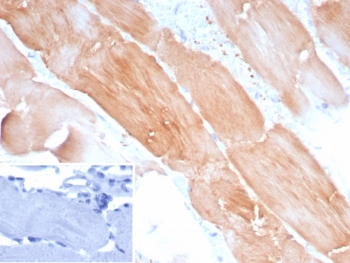

IHC staining of FFPE human skeletal muscle tissue with ACTN2 antibody (clone ACTN2/8184R). Inset: PBS used in place of primary Ab (secondary Ab negative control). HIER: boil tissue sections in pH 9 10mM Tris with 1mM EDTA for 20 min and allow to cool before testing.